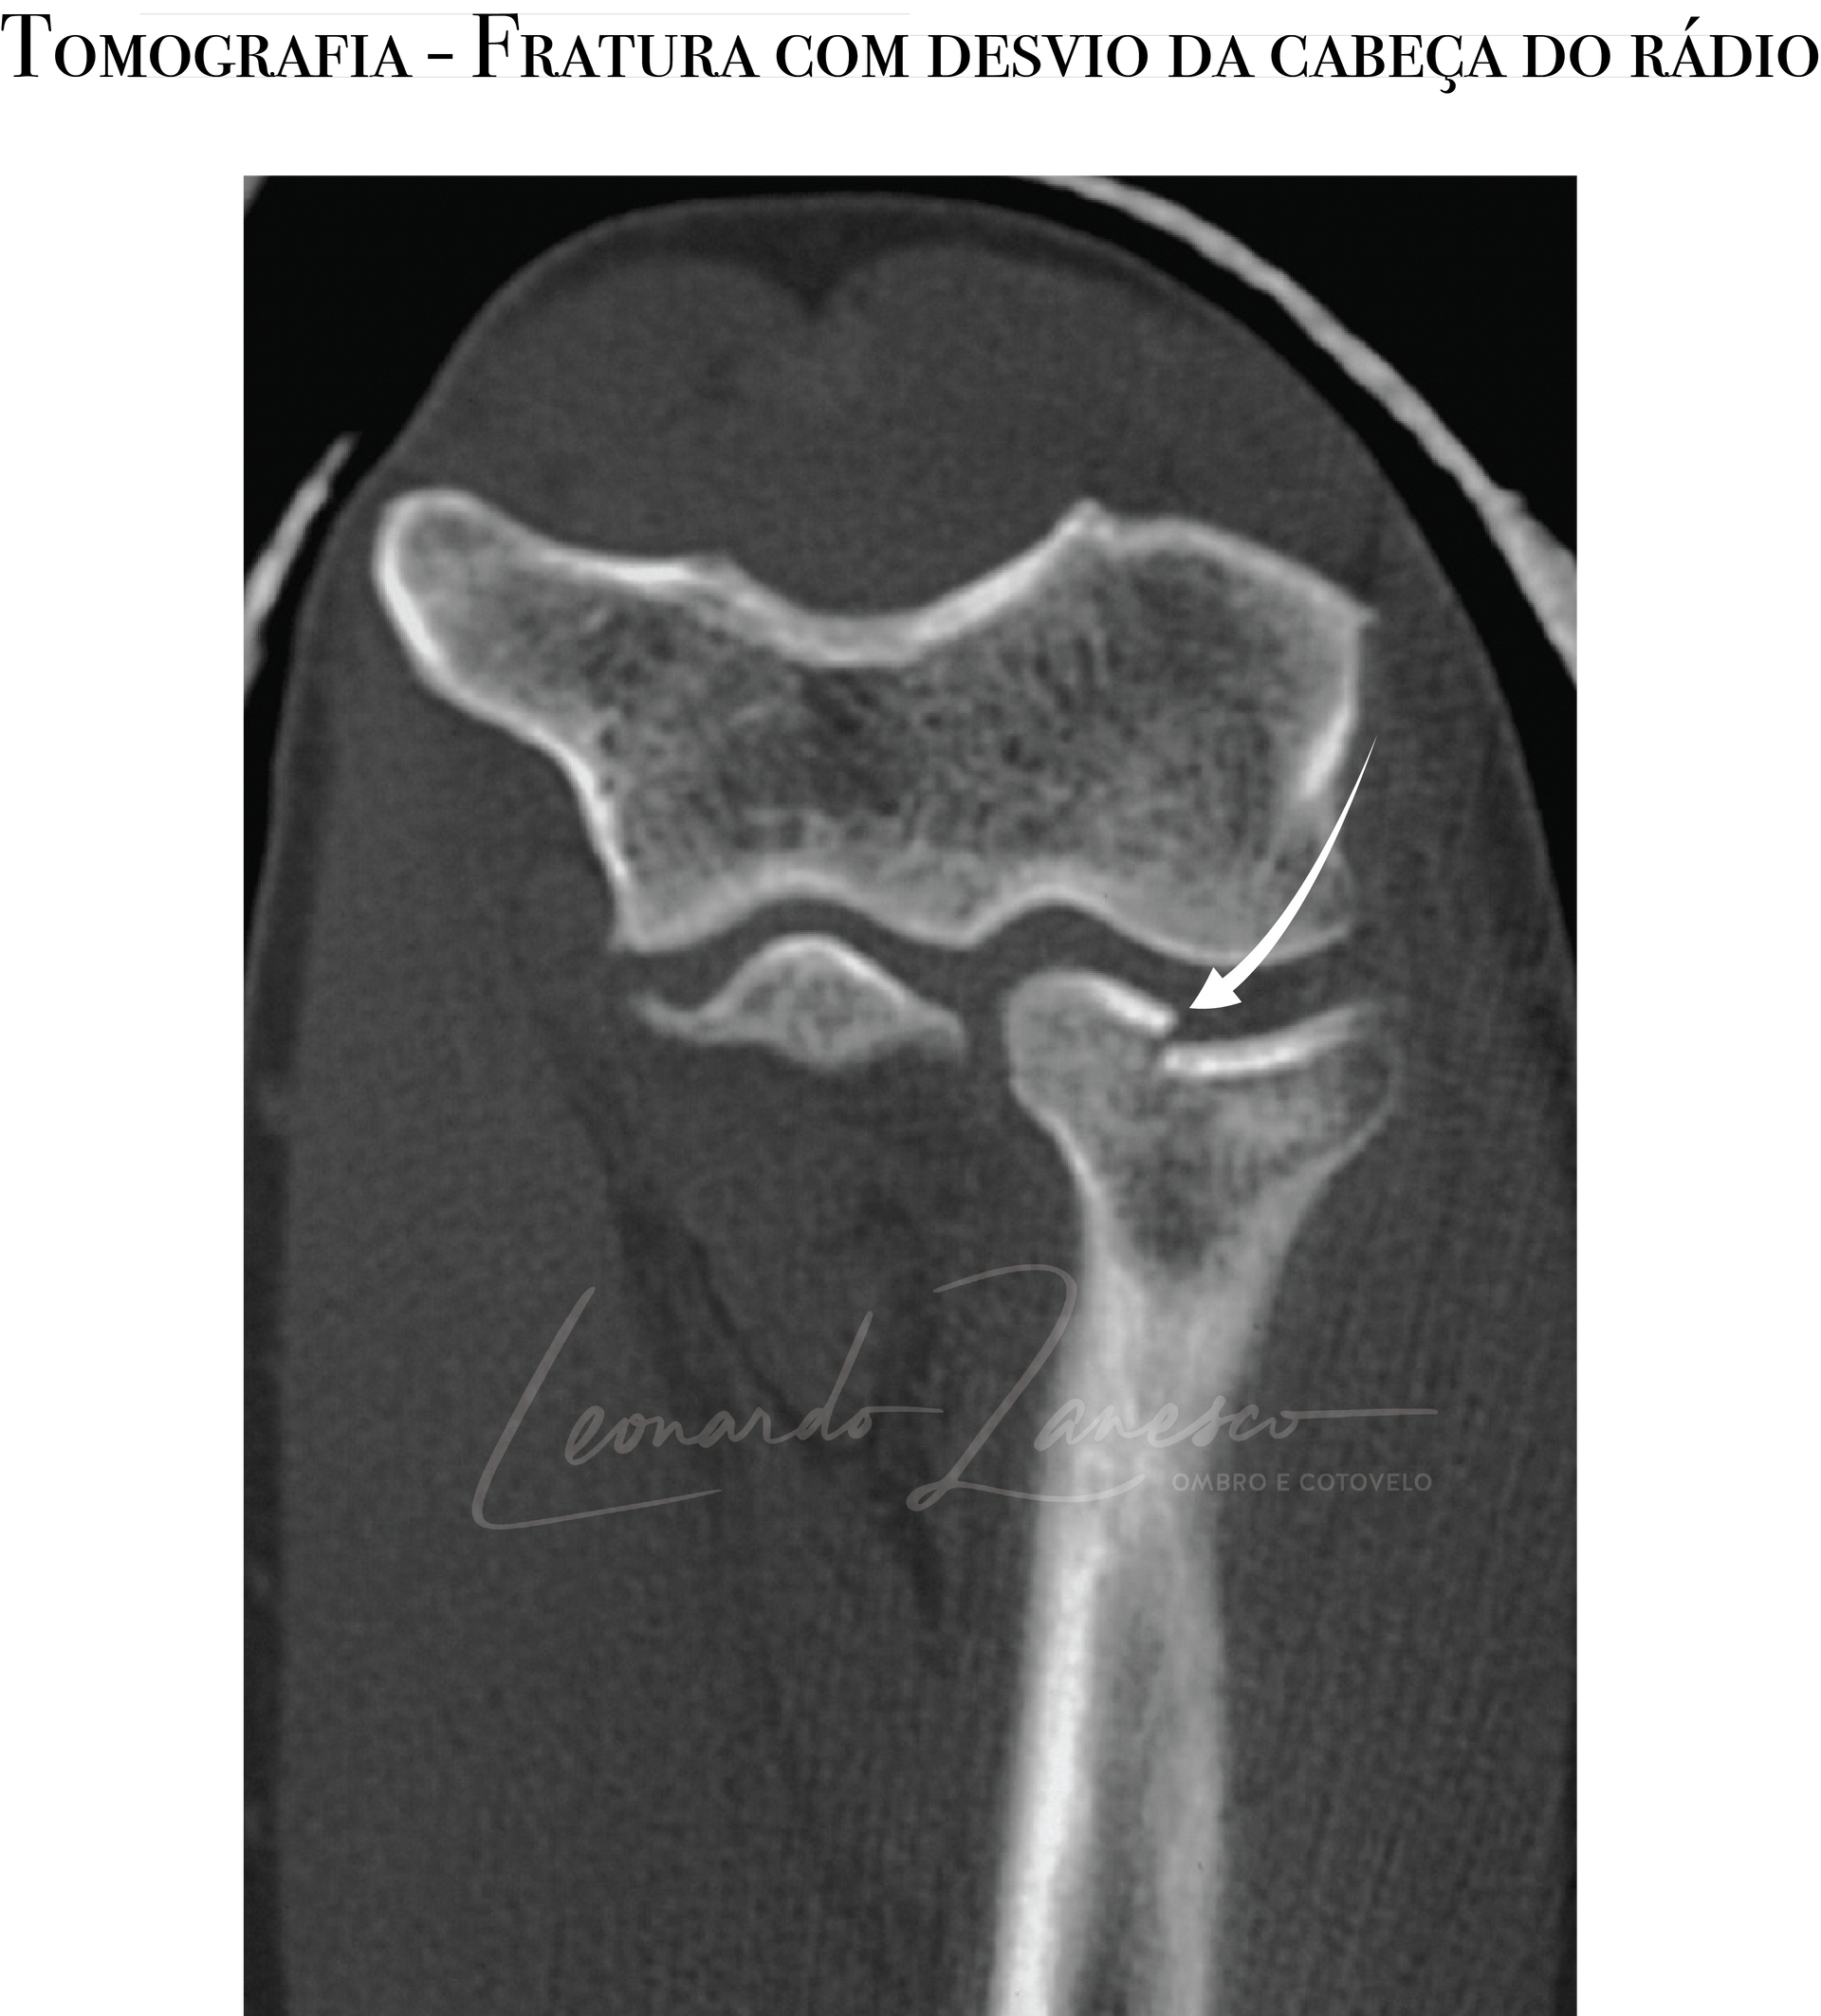

Radiografias em AP e perfil costumam fazer o diagnóstico quando há desvio; nas fraturas sem desvio, os sinais do coxim gorduroso (anterior e posterior) podem ser a única pista inicial. A incidência radiocapitelar ajuda a perfilar a cabeça do rádio. Para definir com precisão o número de fragmentos, localização e grau de desvio — e para pesquisar lesões associadas (coronoide, capitelo, fragmentos osteocondrais) — a tomografia é o método preferencial. Ressonância raramente é necessária na fase aguda.

Tipo II: fratura parcial com deslocamento >2 mm e/ou >30% da superfície articular, podendo gerar bloqueio da rotação.